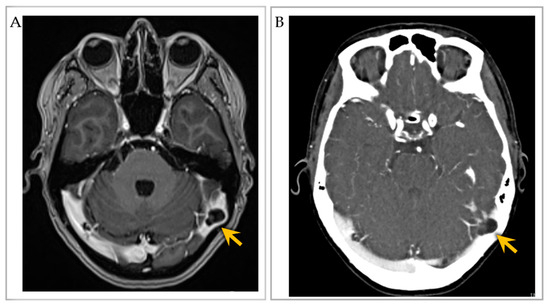

3.7. Imaging Features